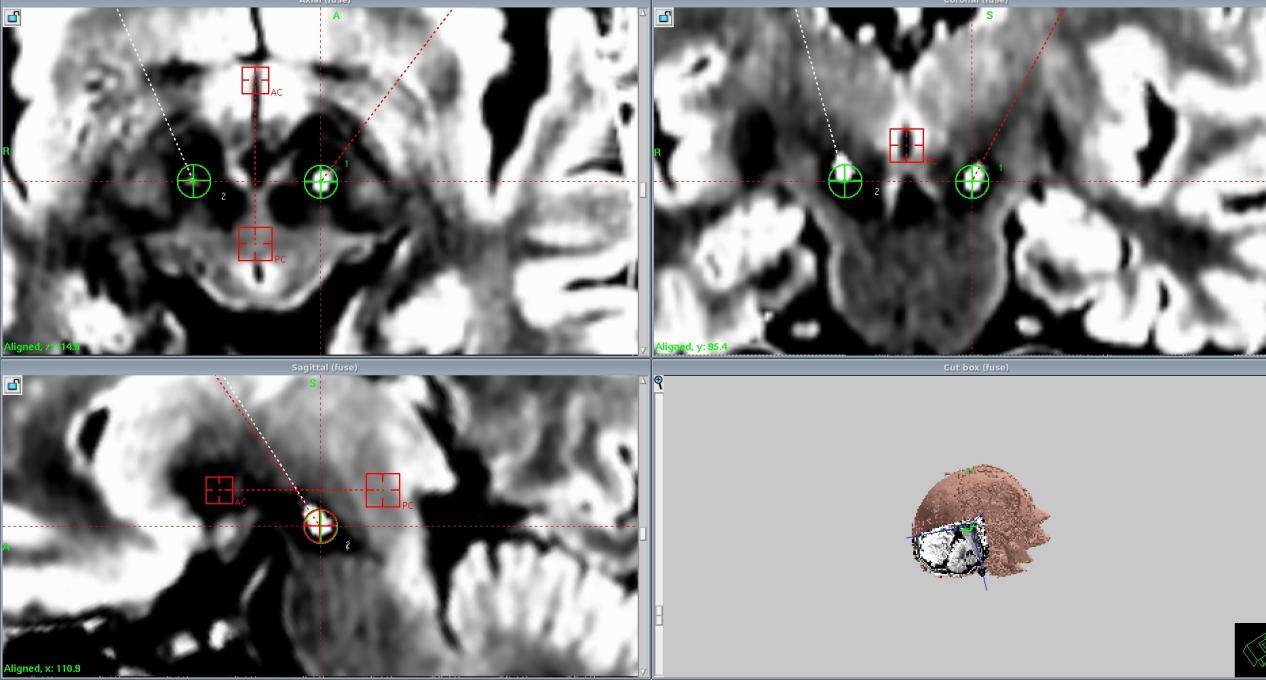

计伟主任带领手术团队,以精湛的技艺和严谨的态度投入到手术操作中。他们借助先进的影像导航技术,精准定位核团靶点,每一个操作都小心翼翼、精准无误。